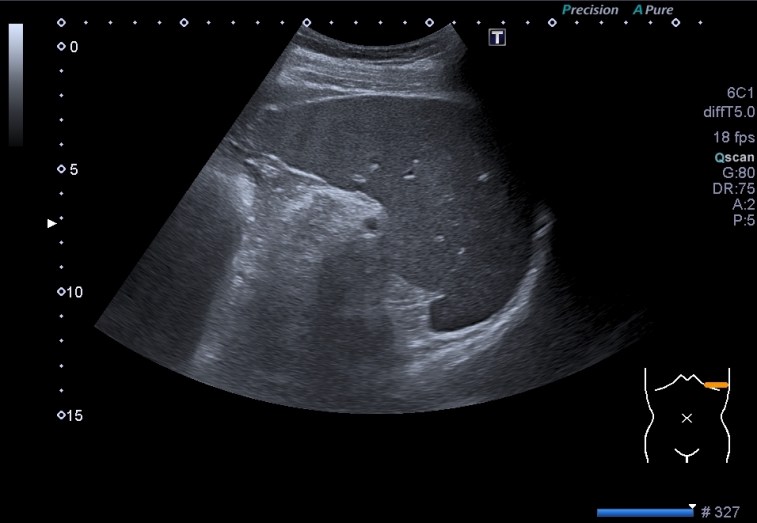

Estas dos imágenes superiores son la normalidad. Corte axial y longitudinal del Bazo. Homogéneo, sin lesiones, grande sin llegar a la esplenomegalia. Bazo de libro.

Toca ahora ver las imágenes patológicas:

Observas, semiólogicamente hablando, un bazo con una gran cantidad de lesiones ocupantes de espacio, hiperecogénicas que afectan a toda la ecoestructura. Doppler normal.